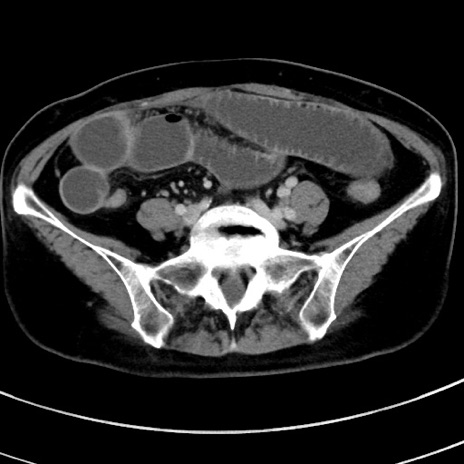

症例9(横断像)

【症例】 60歳代女性

【主訴】むかつき、みぞおちの痛み

【現病歴】3日前よりむかつきがあり、食事がとれない。

【既往歴】糖尿病

【身体所見】発熱なし、心窩部圧痛軽度あるも、腹膜刺激症状なし。

【データ】WBC 7400、CRP 1.92